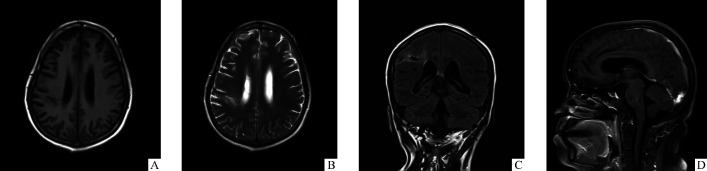

图1.

患者2019年11月22日MRI

Figure 1 MRI of the patient on November 22, 2019

A: Patchy long T1 signal near the posterior horn of the right lateral ventricle. B: Patchy long T2 signal is seen near the posterior horn of the right lateral ventricle; C: T2 FLAIR is low signal, surrounded by visible high signal. D: Sagittal enhancement shows abnormal pia mater enhancement around cerebellar and in cerebral sulcus.

患者,女,54岁,2019年11月19日因“牙龈出血10月余,头痛3月余”就诊于我院风湿免疫科。患者从2019年1月开始无明显诱因出现牙龈自发性出血,轻微刺激即出血较多,难以止住,伴有全身紫癜,不伴有头晕、头痛及鼻出血,无恶心、呕吐等,当时在中国人民解放军第163医院查血小板为4×109/L。于1月25日转至湖南省人民医院住院治疗,入院检查显示:HIV阴性,红细胞计数为2.86×1012/L,血红蛋白为90 g/L,血小板为16×109/L;免疫球蛋白IgG、IgM阳性;抗核抗体(+),抗人球蛋白IgG(++),抗心磷脂抗体IgG、IgA、IgM均为阳性,抗Coombs试验(++)。予以地塞米松磷酸钠(10 mg/d)、免疫球蛋白(20 g/d),以及护胃、止血、输血小板等对症治疗后血小板升至272×109/L,红细胞计数为3.35×1012/L,血红蛋白为106 g/L。于2月1日出院,出院后口服甲泼尼龙片(每次24 mg,每日2次,3周后逐渐减量,每周减4 mg,减至每日4 mg,维持1个月后再停药)。4月16日因血小板减少再次就诊于湖南省人民医院血液科,入院血小板为11×109/L,继续给予与之前相同的治疗后病情好转,4月23日出院,出院后继续服用甲泼尼龙片(每次24 mg,每日2次,每周监测血常规,血小板计数正常后2周开始减量,每周减4 mg,减至每日1片,维持1个月后再停药),并加用硫酸羟氯喹片(每次0.1 g,每日2次)。7月无明显诱因出现阵发性头痛,自诉休息后可稍缓解;8月初头痛程度较前加重,且波及整个头部,为持续性刺痛感,较剧烈,稍感恶心,未呕吐,无发热,未予以重视,自行服用止痛药(具体不详)后稍缓解;9月初突发左侧肢体活动障碍伴麻木,于当地医院完善头部MRI平扫+磁共振血管成像(magnetic resonance angiography,MRA)+扩散加权成像(diffusion- weighted imaging,DWI),结果提示:1)右侧额顶部急性脑梗死;2)轻度脑白质变性,脑萎缩;3)右侧大脑中动脉远端分支血供减少;4)右侧椎动脉细小(先天发育异常)。予以阿司匹林等相关脑梗死对症治疗(具体不详)后出院。10月16日就诊于北京协和医院门诊,查LA为2.5(参考值范围≤1.2),β2-GP1抗体IgM>841 AU/mL(参考值范围<20 AU/mL),ACA IgM为87.4 MPLU/mL(参考值范围<10 MPLU/mL),APS诊断明确,予以羟氯喹片(每次0.1 g,每日2次)、他克莫司(每次1 mg,每日2次)、阿司匹林肠溶片(每次0.1 g,每日1次)、阿托伐他汀钙片(20 mg,每晚1次)及醋酸泼尼松片(10 mg,每日1次)。患者因头痛加剧,11月21日于我院风湿免疫科完善腰椎穿刺,提示压力为400 mmH2O(1 mmH2O=0.098 kPa),脑脊液微生物学检查结果为墨汁染色阳性。患者多次腰椎穿刺结果见表1。HIV阴性。11月22日头部MRI诊断意见:1)右侧侧脑室后角旁异常信号影,考虑软化灶形成并周围胶质增生;2)脑白质病变,脑萎缩;3)颅内动脉硬化,右侧椎动脉狭窄可能;4)双侧部分胚胎型大脑后动脉;5)双侧颈内动脉、窦汇未见显影,右侧橫窦、乙状窦、上下矢状窦细小,直窦显影浅淡(图1)。在风湿免疫科治疗时给予甲泼尼龙片(每次8 mg,每日1次)和羟氯喹片(每次0.2 g,每日1次)抗炎、抗风湿,低分子肝素钙注射液(5 000 U,每日1次,皮下注射)抗凝,甘露醇(125 mL,每6 h 1次,静脉滴注)、甘油果糖(250 mL,每12 h 1次,静脉滴注)和托拉塞米(10 mg,每日1次,静脉推注)降颅压,左乙拉西坦(500 mg,每12 h 1次)抗癫痫。于11月25日转入神经内科监护室后继续脱水降颅压,当日加用两性霉素B静脉滴注和鞘内注射(0.1 mg,1次)、氟胞嘧啶(0.5 g,每日3次)抗真菌治疗,其中两性霉素B静脉滴注的起始剂量为每日5 mg,后每日增5 mg,最终以每日50 mg维持至12月11日,因顽固性电解质紊乱,12月12日将两性霉素B 50 mg开始改为两性霉素B脂质体每日40 mg静脉滴注。11月26日脑脊液培养可见新型隐球菌。12月12日复查头部MRI,结果提示:1)右侧侧脑室后角旁-右额顶叶交界区软化灶并胶质增生、轻度脑积水,情况大致同前;小脑周边及脑沟内异常的脑膜强化减少;2)脑白质病变、脑萎缩,情况大致同前(图2)。12月15日开始两性霉素B脂质体加量至每日50 mg静脉滴注,2020年1月15日增至60 mg,1月17日药剂科会诊后加用氟康唑(400 mg,每日1次)抗真菌。期间,针对APS原发病继续采用抗炎、抗风湿、抗凝等治疗。2020年1月25日血红蛋白为101 g/L;2月1日血红蛋白降为84 g/L;2月10日血红蛋白为70 g/L,血小板为95×109/L,并出现发热(最高体温达38.5 ℃)和反复发作性心力衰竭;2月11日复查血红蛋白为58 g/L,血小板为73×109/L。家属因经济原因于2020年2月12日转回当地医院治疗,之后电话随访,患者2月14日于当地医院死亡。